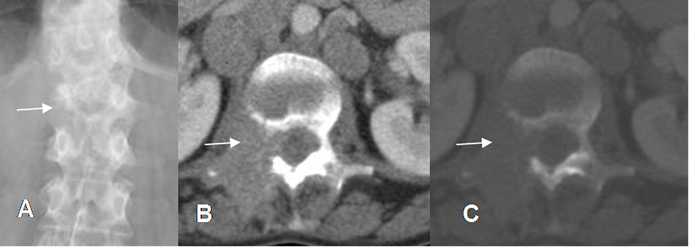

Fig 152. Metástasis líticas.

A: Rx AP. Pérdida en la configuración del pedículo derecho de L1.

B: TAC axial en ventana de tejido y C: en ventana osea. Enfermedad metastásica con destrucción del pedículo vertebral, un hallazgo descrito clásicamente.